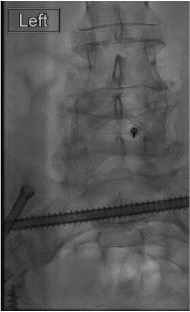

Contrast injection — "Christmas tree"

Inject steroid + anesthetic